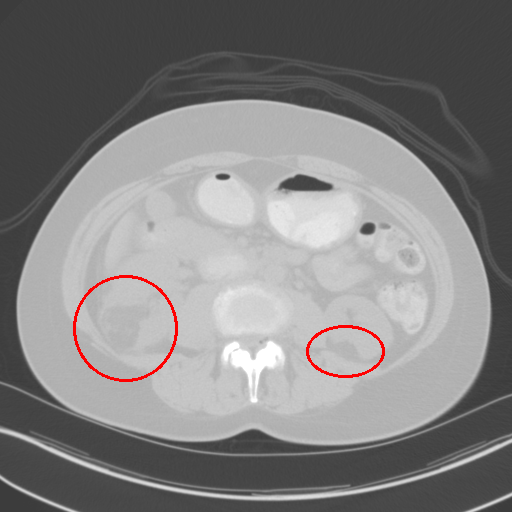

(d) [446, 1960]

Figure 1: CT images under different window level and window width. (a) is the image used in 3DCE. (b),(c),(d) are the multi-view images used in our MVP-Net.

To accommodate for network input, previous studies [5, 6] use a significantly wide window222Windowing, also known as gray-level mapping, is used to change the appearance of the picture to highlight particular structures. to compress CT’s 12bit Hounsfield Uint (HU). However, this would severely deteriorate the visibility of lesions as a result of degenerated image contrast, as shown in Fig.1(a). In the clinical practice, fusing information from multiple windows are effective in improving the accuracy of detecting subtle lesions and reducing false positives (FPs). During visual inspection of the CT images, radiologists would combine complex information of different inner structures and tissues from multiple reconstructions under different window widths and window levels to locate possible lesions. To imitate this process, we propose to extract prominent features from three frequently examined window widths and window levels and capture complementary information across different windows with an attention based feature aggregation module.

The multi-view input for the MVP-Net is composed of multiple reconstructions under different window widths and window levels. Specifically, we adopt k-means algorithm to cluster the recommended windows (labeled by radiologists) in the DeepLesion dataset and obtain three most frequently inspected windows, whose window levels and window widths are [50,449]50449[50,449], [505,1980]5051980[-505,1980] and [446,1960]4461960[446,1960] respectively. As shown in Fig.1, these clustered windows approximately correspond to the soft-tissue window, lung window, and the union of bone, brain, and mediastinal windows respectively.

We also perform a case study to analyze the importance of multi-view modeling. As shown in Fig. 3, the model indeed benefits from the multi-view modeling: the lesions that are originally indistinguishable in the view of 3DCE due to the wide window range and lack of contrast, now becomes distinguishable under the view of appropriate windows. Thus our model presents better identification and localization performance.